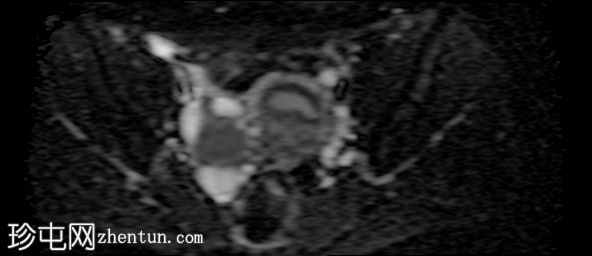

冠状位

T2加权像

在右侧附件区可见一较大病灶,最大轴位和头尾径约为3 x 3.8 x 3.7 cm。该病灶在T1加权像上呈高信号,脂肪抑制像上无信号抑制,在T2加权像上呈低信号(阴影效应)。病灶壁可见T2暗点征结节,增强扫描后未见明显强化。

右侧附件区可见两个较小的类似病灶,最大径约1.2 cm。

此外,右侧附件区可见一扩张的管状结构,最大轴向和头尾径约6.3 x 2.1 x 5.2 cm。

该结构T1呈低至中等信号,T2呈高信号,分隔不完整。增强扫描未见明显强化,符合输卵管积水表现。

所描述的右侧附件病灶具有典型的子宫内膜异位囊肿MRI特征,包括T1高信号(无脂肪抑制)和T2低信号(阴影)。T2暗点征的存在进一步支持慢性出血性内容物。

相关的较小病灶可能代表其他子宫内膜异位种植灶。

扩张的管状结构伴有T2高信号和不完全分隔,符合输卵管积水的表现,输卵管积水常见于盆腔子宫内膜异位症。少量邻近游离液体通常为反应性积液。